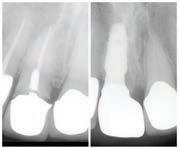

Christopher Chung, DMD

Smile Again Dental Group 818-776-9300

์์น์ง์ ๋ง์น๊ณ ๋์ ๊ฐ๊ธ ํ ๋ฒ ํ๋ฉด, ์

์์ด ํจ์ฌ ๊ฐ์ดํด์ง๊ณ ์์พํ ์ฃ . ์ฌ์ค ๊ฐ๊ธ์ ๊ทธ๋ฅ ์๋ฌด๊ฑฐ๋ ์จ๋ ๋ค ๋น์ทํ ๊ฒ ๊ฐ์ง๋ง, ์ฑ๋ถ๊ณผ ์ฉ๋

์ ๋ฐ๋ผ ๊ฝค ํฐ ์ฐจ์ด๊ฐ ์์ต๋๋ค. ์ด๋ค ๊ฐ๊ธ์ด ์น์ ๊ฑด๊ฐ์ ๋์์ด ๋๋ ์ง, ๋ ์ธ์ ์ด๋ป๊ฒ ์ฌ์ฉํ๋ ๊ฒ ์ข์์ง ์กฐ๊ธ ๋ ์์ธํ ์ ๋ฆฌํด๋ดค์ต๋ ๋ค.